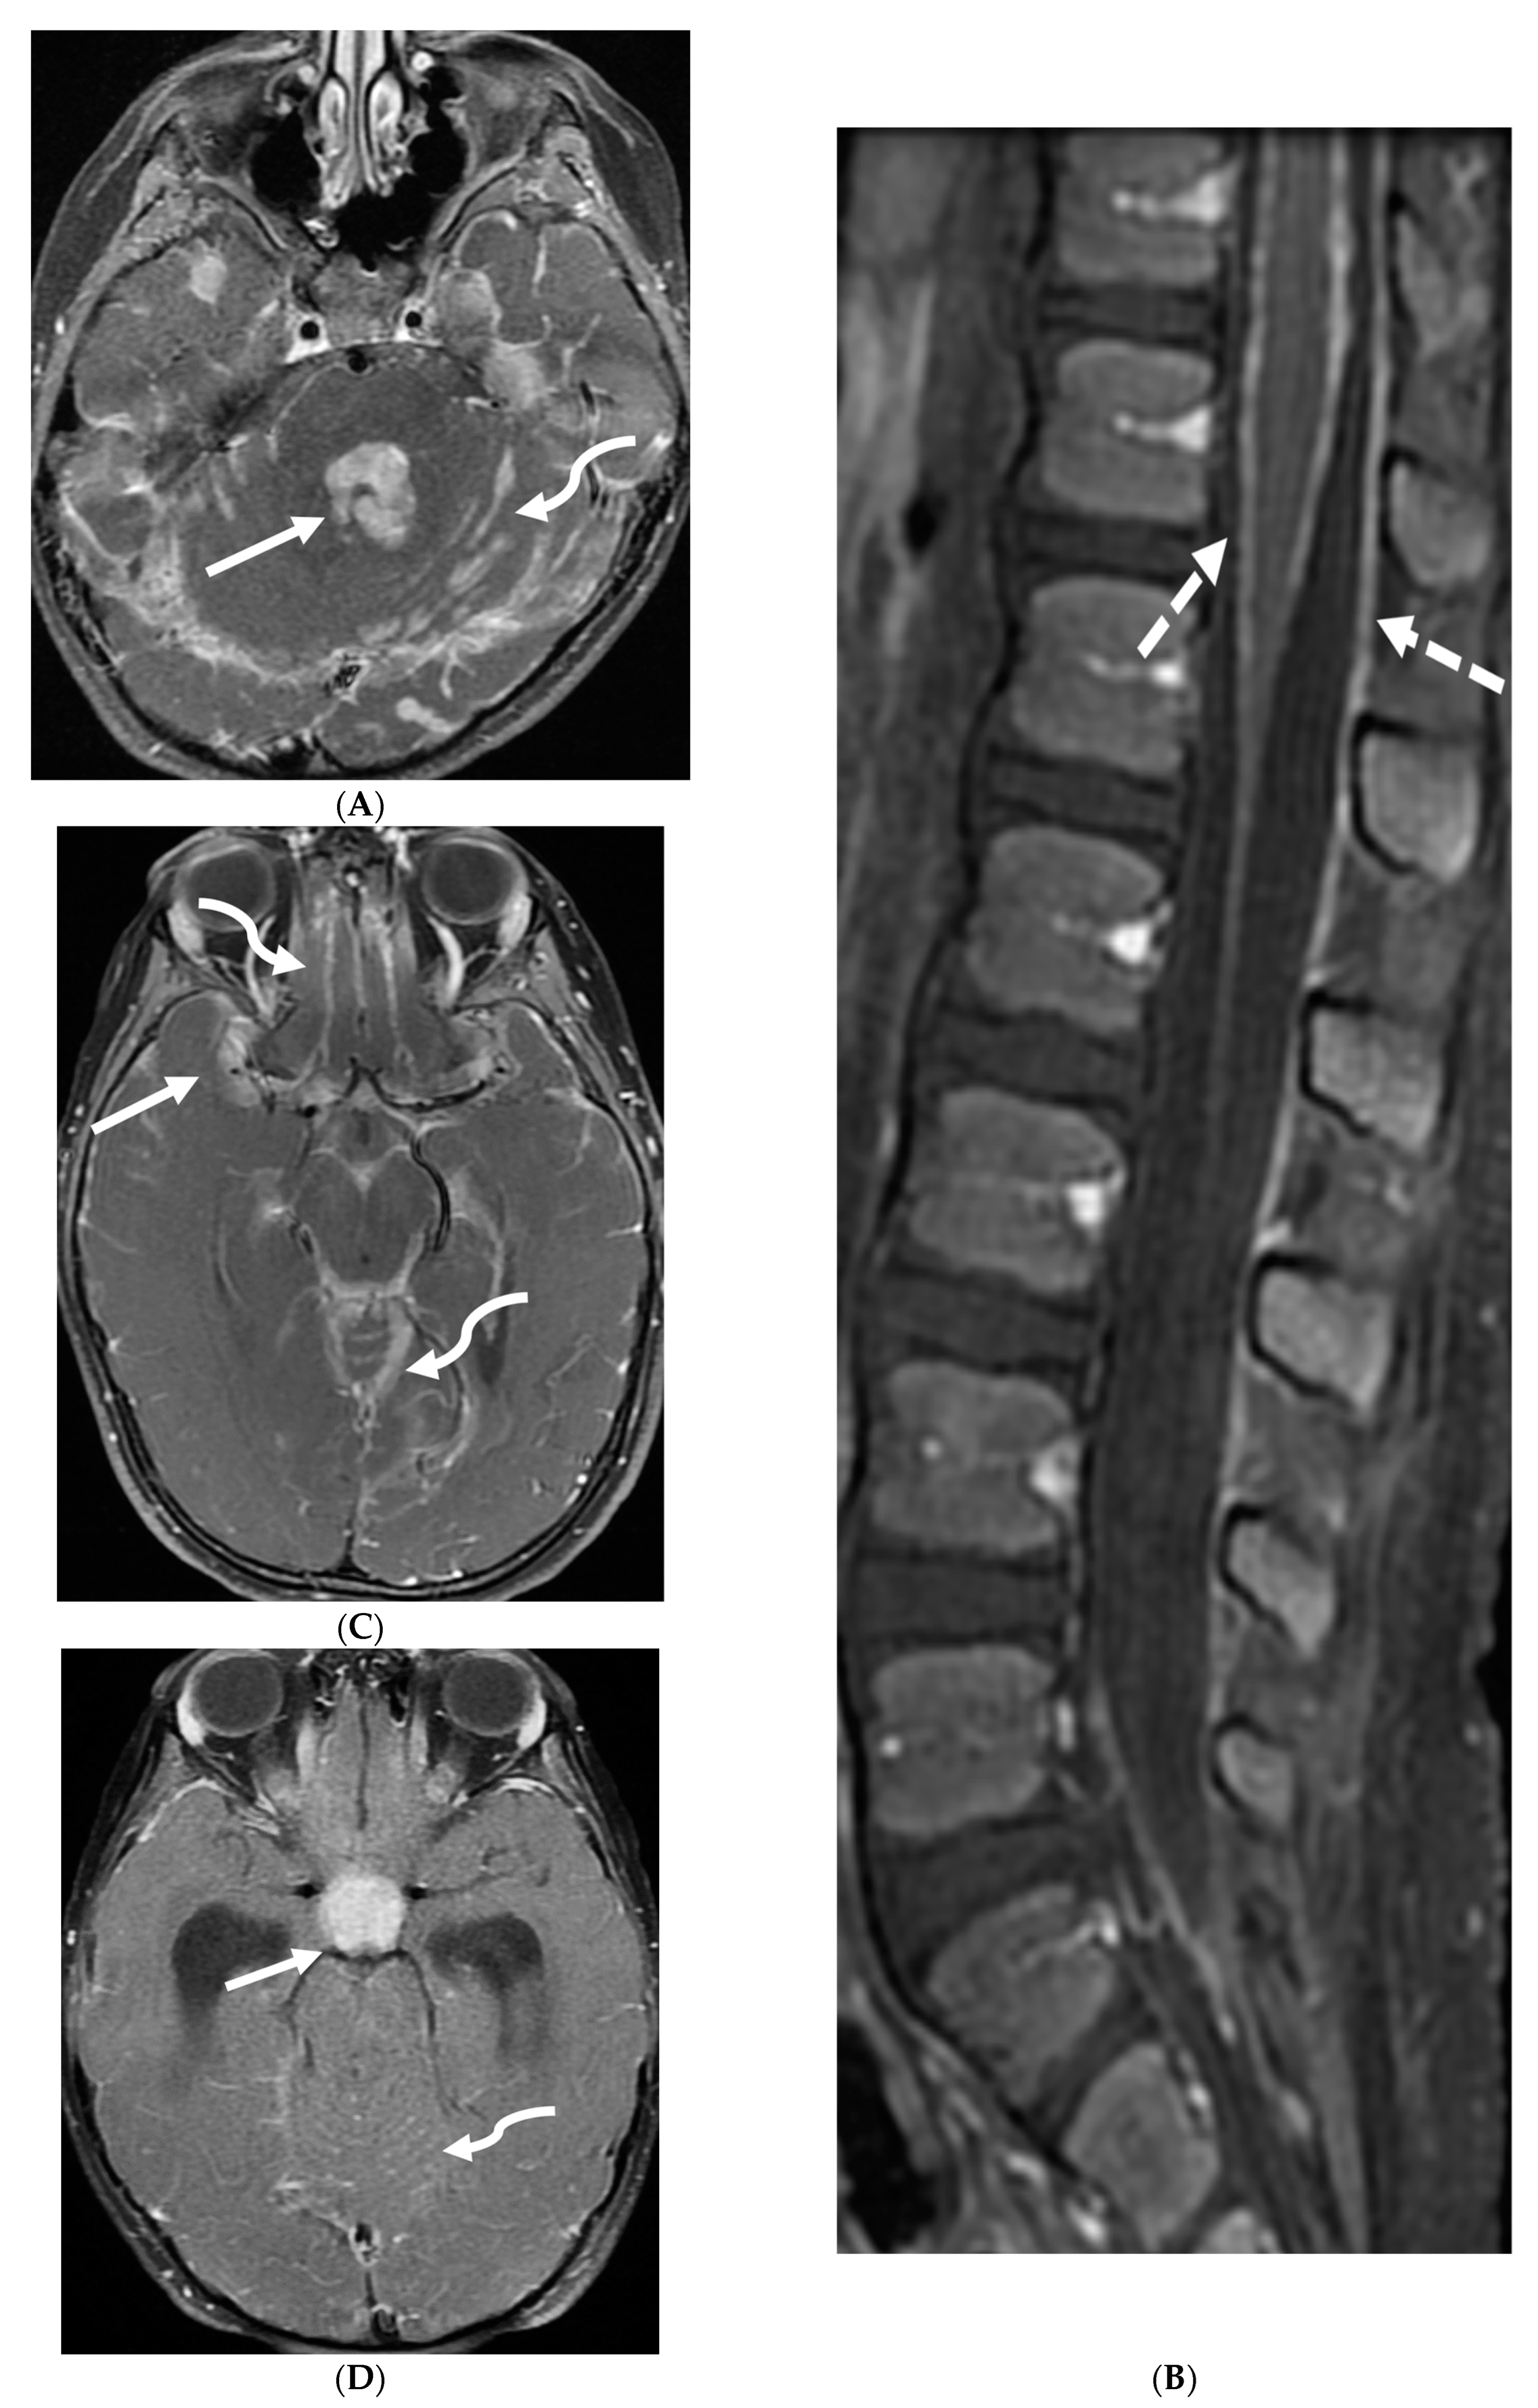

The most characteristic MRI findings in GBS are smooth contrast enhancement of the spinal nerve roots with variable thickening, particularly in the cauda equina region (Figure 4). Selective or prominent anterior nerve root enhancement favors the diagnosis of GBS [32,33]. A higher incidence of cranial nerve abnormalities, particularly the optic nerve, is seen in children with the GBS variant, Miller Fisher syndrome (MFS) [34,35]. Ultrasound imaging of peripheral nerves offers a promising new tool for early GBS diagnosis by detecting enlarged cervical nerve roots early in the disease course [36,37].

Figure 4.

Post contrast sagittal T1 (A) and axial T1 (B) of the lumbar spine, post contrast axial T1 of the brain (C,D): 14-year-old girl with numbness/tingling, paresthesia and bilateral lower extremity weakness. Patient also has bilateral facial weakness. There is diffuse mild thickening of the cauda equina nerve fibers with enhancement (arrows). Additionally, exiting nerve roots of the cervical and thoracic region also show enhancement. Enhancement of bilateral facial (dashed arrows) and trigeminal nerves is also visualized (curved arrows). Features are in keeping with Guillain-Barre syndrome (acute inflammatory demyelinating polyneuropathy). With involvement of facial and trigeminal nerves, Miller Fisher variant should be considered.